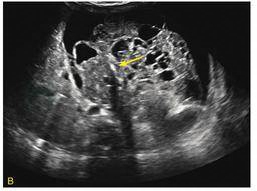

成熟型腹膜后畸胎瘤声像表现为囊实混合性肿块,边界清晰,可有脂液分层及钙化强回声团伴后方声影(图3)。超声显示含有脂肪和钙化的团块,提示畸胎瘤。巨大腹膜后畸胎瘤可压迫肾脏、输尿管,引起尿路梗阻,或使腹主动脉、下腔静脉位移。

图3 腹膜后畸胎瘤

A.右肾受压,肾盂轻度扩张;B.团块内有钙化强回声(箭头)